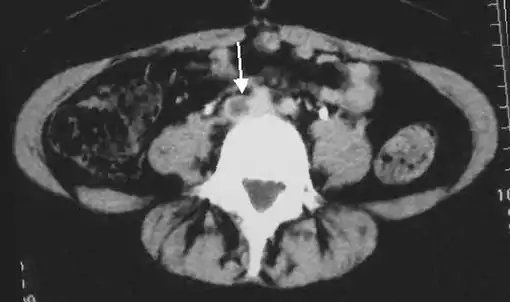

CT scan venography, MRI venography, or a non-contrast MRI are also diagnostic possibilities.[121] The gold standard for judging imaging methods is contrast venography, which involves injecting a peripheral vein of the affected limb with a contrast agent and taking X-rays, to reveal whether the venous supply has been obstructed. Because of its cost, invasiveness, availability, and other limitations, this test is rarely performed.[39]

An abdominal CT scan demonstrating an iliofemoral DVT, with the clot in the right common iliac vein of the pelvis